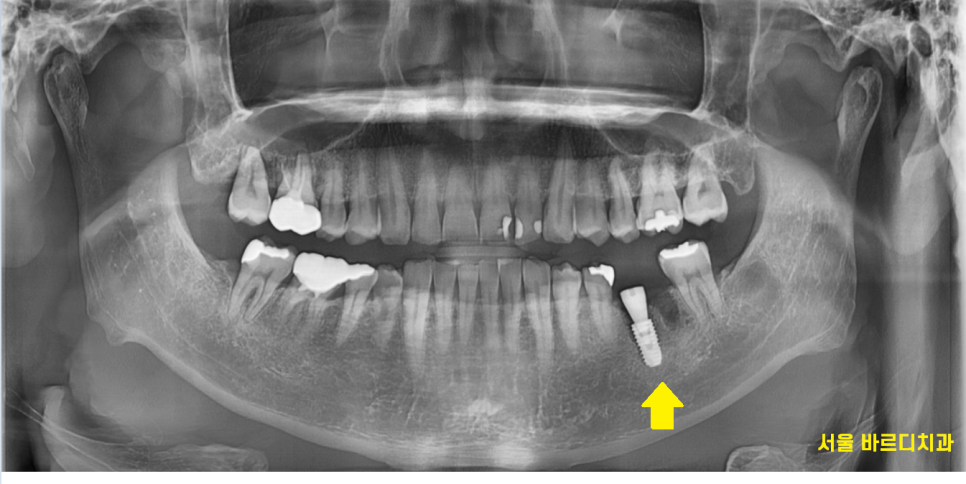

23.10.17

"환자분 혹시 치료할 때 딱딱한 음식 피하라고 들으시지 않으셨나요~?"

x-ray 사진을 보면서 다시 여쭤보았습니다.

왜냐면 치아가 남아있는 양이 별로 없을 때

기둥을 세워 보강하는데

2개나 있었거든요ㅠㅠ

그만큼 남아있는 치아의 양이 없다는 것으로

치아가 약했다는 것을 뜻합니다.

치아뿌리 파절이 수직으로 쫘악 금이가서

부러짐 발생했습니다.

이런 경우 치료 방법이 발치하는 수밖에 없는데